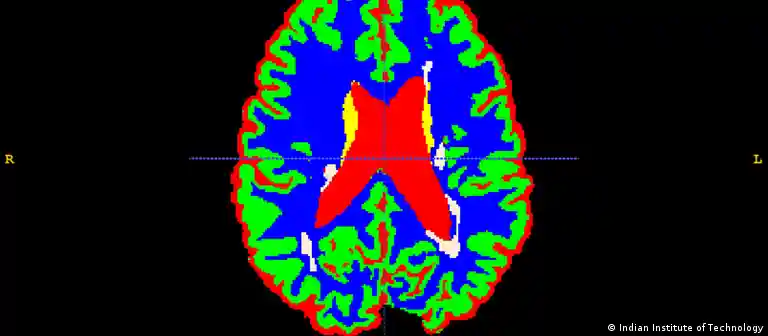

Indien Multiple Sklerose

صورة من: Indian Institute of Technology

التصلب المتعدد

التصلب المتعدد أو التصلب اللويحي هو مرض يصيب الجهاز العصبي للإنسان ويظهر فجأة. ويختلف تطور هذا المرض من مريض لآخر، فبينما يعيش مرضى معه دون أي أعراض تذكر، يضطر آخرون إلى اللجوء لكرسي متحرك بعد سنوات قليلة فقط.